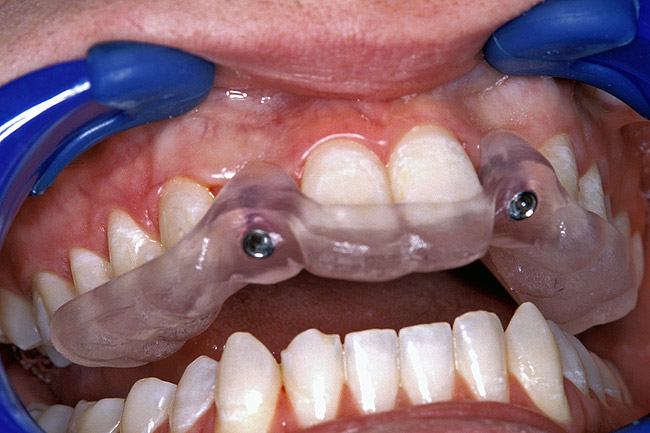

Before the day of surgery, the patient was seen by the orthodontist for the removal of the orthodontic brackets. The patient still was not pleased with the position of the two centrals, and it was determined that this would be addressed after implant placement (Figure 13A). The anatomical variations of the crestal tissue and lack of interdental papilla can be appreciated in the close-up views of the right and left sites (Figure 13B and 13C). There were no surprises on the day of surgery as all of the decisions were made during the planning phase, before the scalpel ever touched the patient. The occlusal view of the CT 3D model revealed the wider alveolar ridge on the right side and thinner crest on the left side (Figure 14A). This was confirmed when the full thickness mucoperiosteal flaps were elevated, and the underyling bone revealed (Figure 14B). The tooth-borne templates were designed to facilitate the drills and drilling sequence specific to the diameters of the predetermined implants (Figure 15A). Each template contained an embedded 5-mm long stainless steel tube, which was approximately 0.2-mm wider than each drill (just wide enough to allow for the drills to rotate freely). Once positioned over the natural teeth, the template was secure and offered precision accuracy in transferring the implant locations from the original software-designed plan, allowing the potential for internal and external irrigation (Figure 15B). The 3.7-mm diameter Tapered Screw-Vent implant drilling sequence requires three drills: pilot, intermediate, and final sizing. Thus, three separate templates were fabricated to a.commodate these sizes. The templates were removed easily and replaced with the next sequential size in less time than it takes to change the drill on the surgical handpiece. After the osteotomies had been.completed, the implants were delivered to the site (Figure 16A and Figure 16B). For this internal hex connection implant, the author r.commends that the flat of the antirotational hex be positioned to the facial for proper orientation of the restorative.components (Figure 17A). Preprepared margins were created from a milled titanium fixture mount transfer post, which was delivered to the implant as support for an immediate transitional restoration. The facial “dot” helped confirm the orientation of the abutment to the facially positioned flat side of the internal hex connection (Figure 17B). Before cementation of the transitional acrylic restorations, a closed-tray, fixture-level impression was made, and a soft-tissue model fabricated.

Figure 13a  Before implant surgery, the orthodontic brackets were removed, revealing (A) the position of the centrals, and (B, C) the anatomical variations of the crestal tissue and lack of interdental papilla.

Figure 13a

Figure 13b  Before implant surgery, the orthodontic brackets were removed, revealing (A) the position of the centrals, and (B, C) the anatomical variations of the crestal tissue and lack of interdental papilla.

Figure 13b

Figure 13c  Before implant surgery, the orthodontic brackets were removed, revealing (A) the position of the centrals, and (B, C) the anatomical variations of the crestal tissue and lack of interdental papilla.

Figure 13c